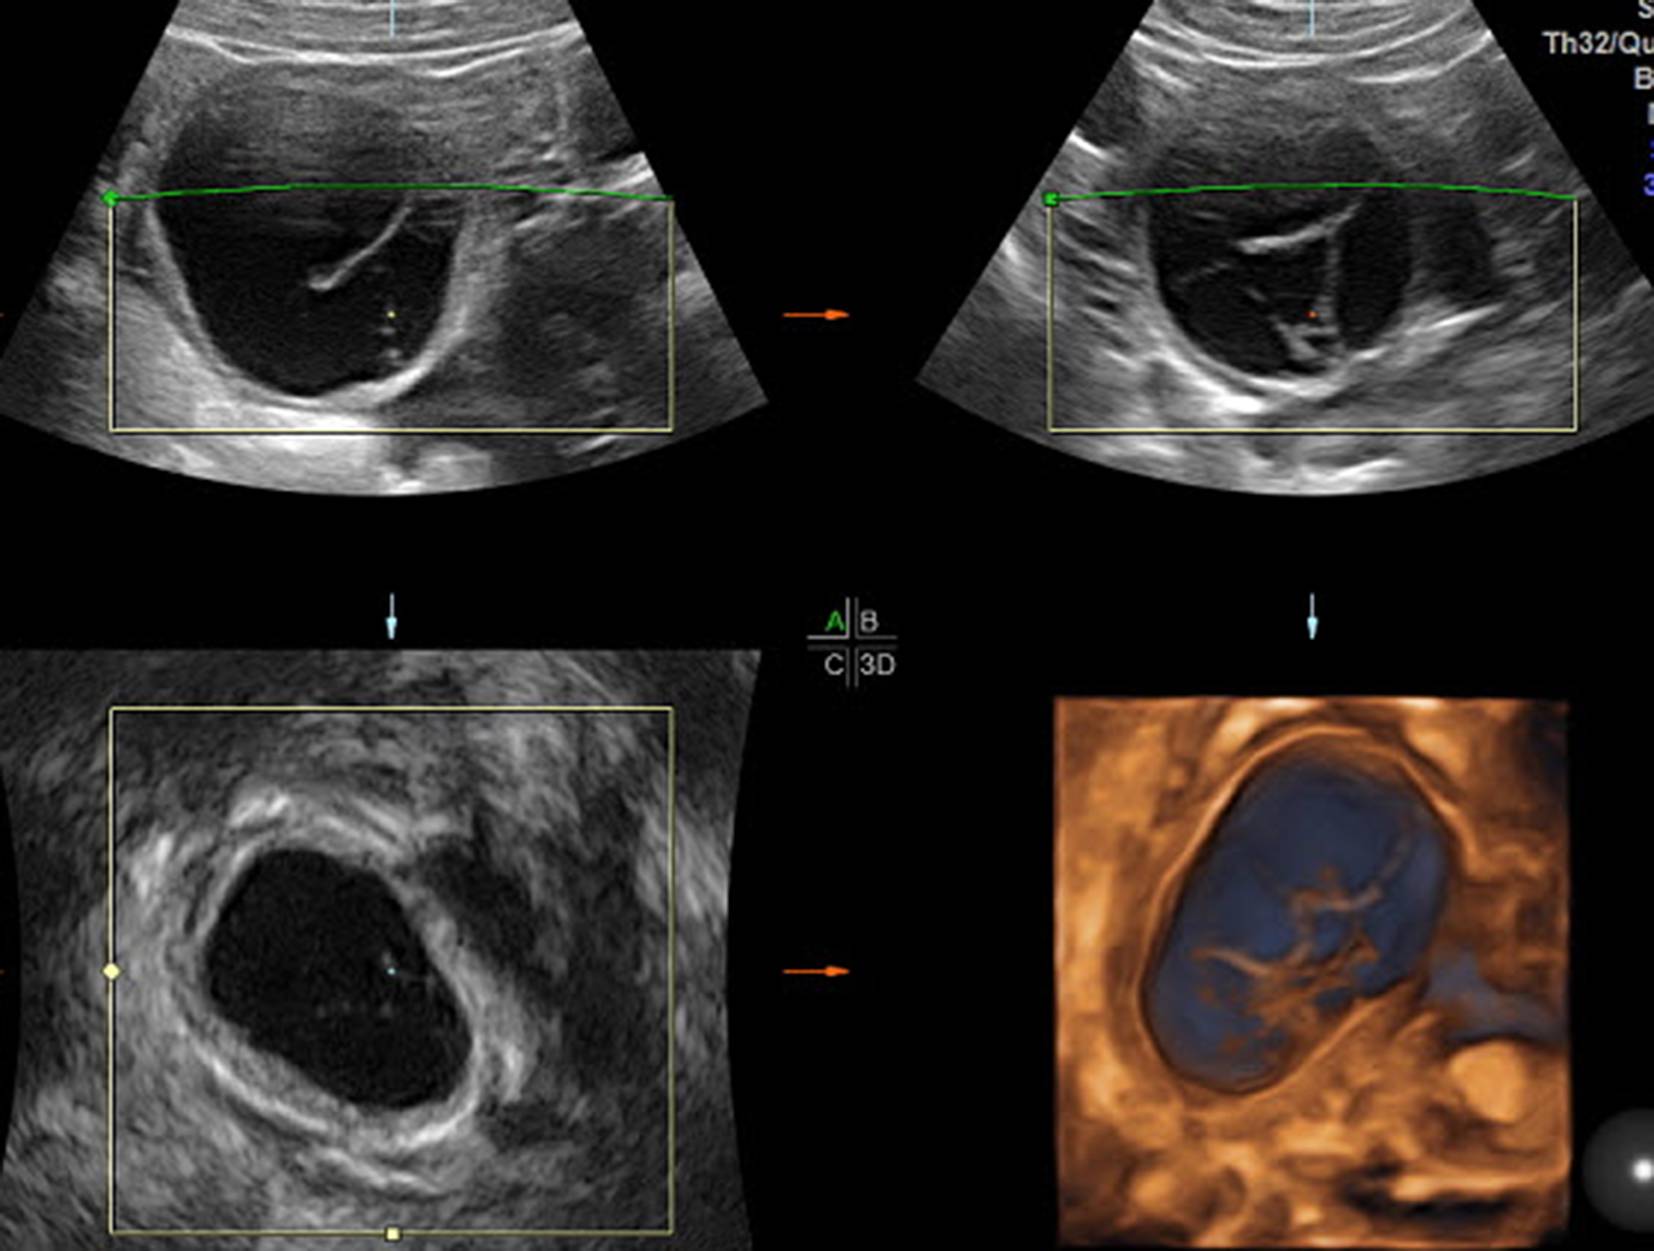

Abb. 8

a Medikamentös stimuliertes Ovar am 12. Zyklustag mit einem 15 mm-Follikel von abdominal geschallt. b Die Anwendung des 3‑D-Schalls zeigt die im B‑Mode nicht so gut erkennbaren Follikel und hilft bei der Entscheidung, ob in diesem Zyklus eine Ovulation ausgelöst werden soll oder nicht